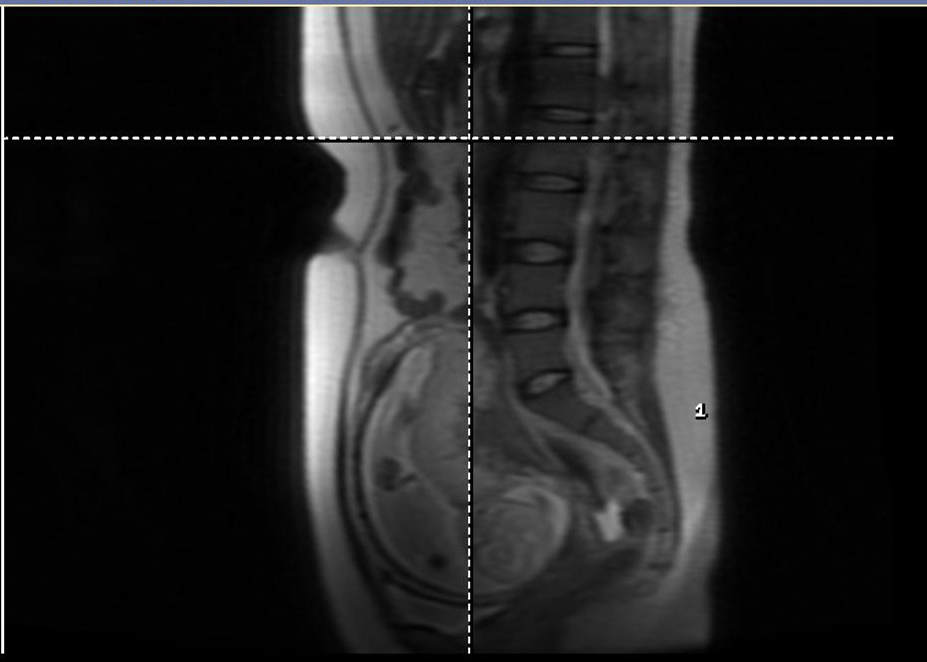

右肾肿物(MRI水平位)

胎儿(MRI)

放射科结合MRI表现考虑肾脏肿物恶性肿瘤可能性很大,并且肾周可见血肿形成。考虑肿瘤可能生长迅速,压迫肾脏导致出血形成肾周血肿,更加坚定了我们手术的想法。但目前缺乏肾脏肿物的病理结果,如果围术期患者发生流产,术后病理为良性肿瘤,医生将承受巨大的压力。超声诊断科提出可以考虑进行超声引导下肿物穿刺活检,病理科医生认为肿物穿刺活检取材有限,明确诊断可能性不高,而且存在肿瘤针道转移、出血风险。